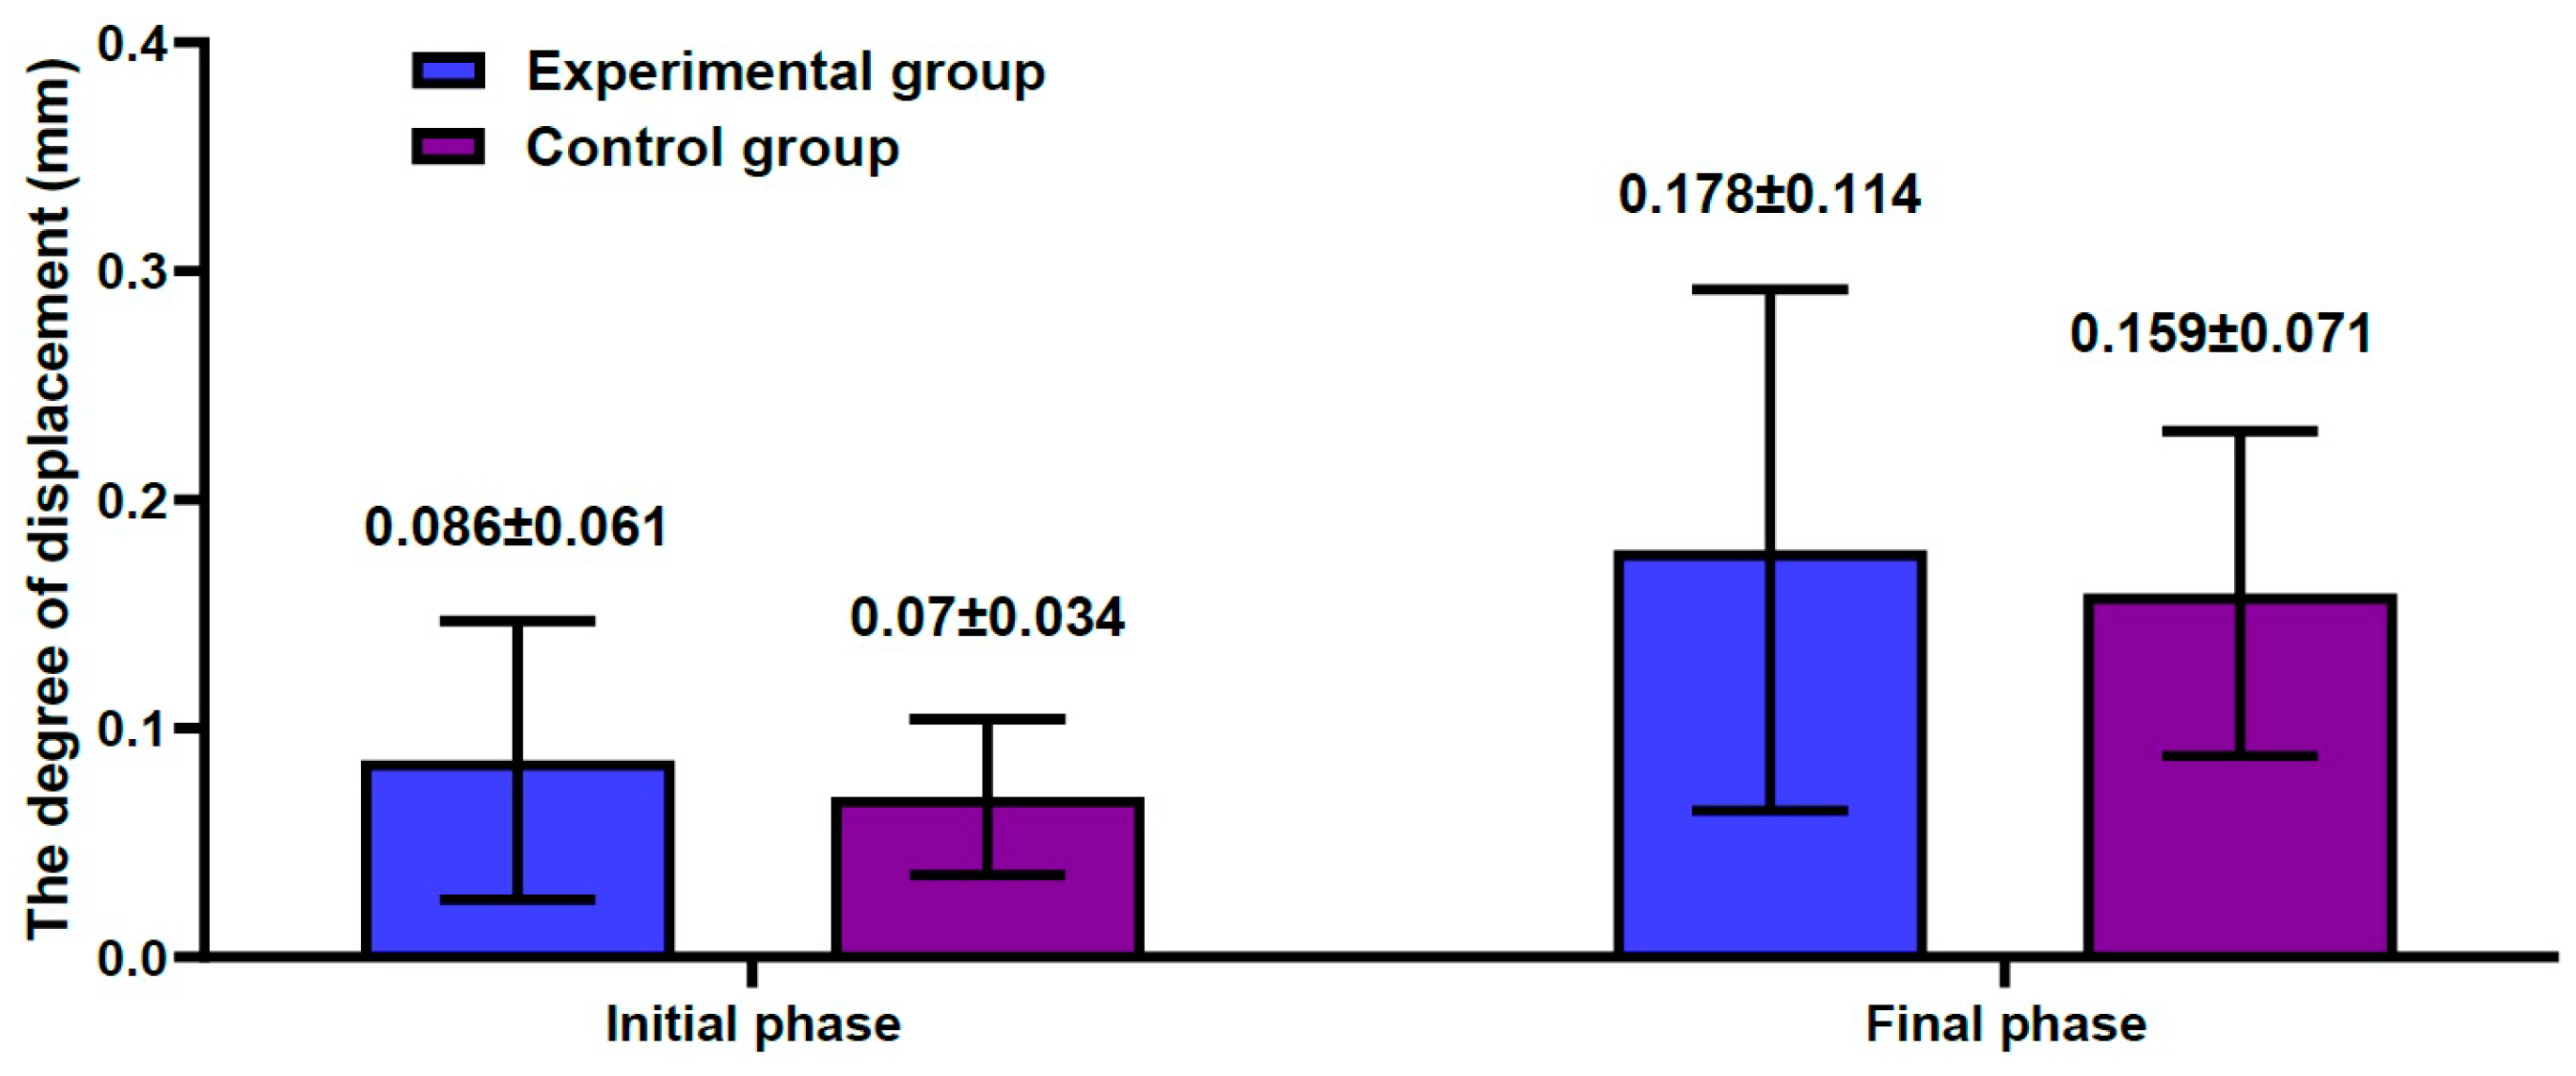

3.2. Results of the Biomechanical Study

3.3. The Bond Strength at the Bone–Cement Interface